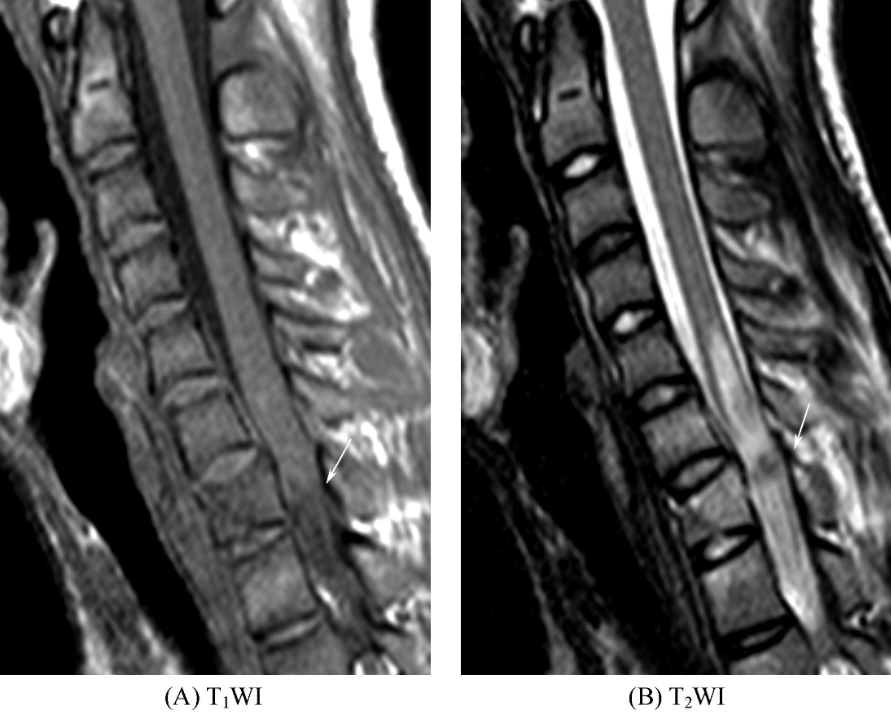

①椎体爆裂骨折。椎体呈楔形,矢状位和冠状位显示椎体上下缘皮质骨低信号带失去完整性,凹凸不平或部分嵌入椎体。椎体内信号改变,T1WI上呈低信号,T2WI上呈高信号,为渗出和水肿所致。骨折线于T1WI及T2WI上均表现为线状低信号影(图3),横断位可见骨折片向各个方向移位。

图3 椎体爆裂骨折胸7椎体楔形变,T1WI上信号减低,T2WI上信号增高,内见线状短T1长T2信号影,胸5~胸8椎体水平脊髓内见条片状长T1长T2信号影。